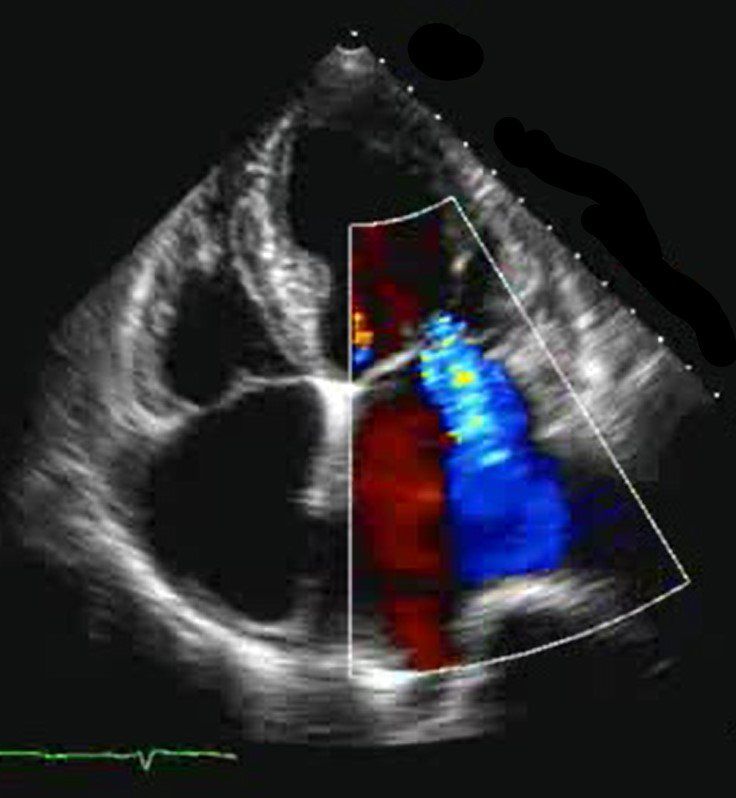

- Ultraschalluntersuchungen des Herzens (Echokardiographie)